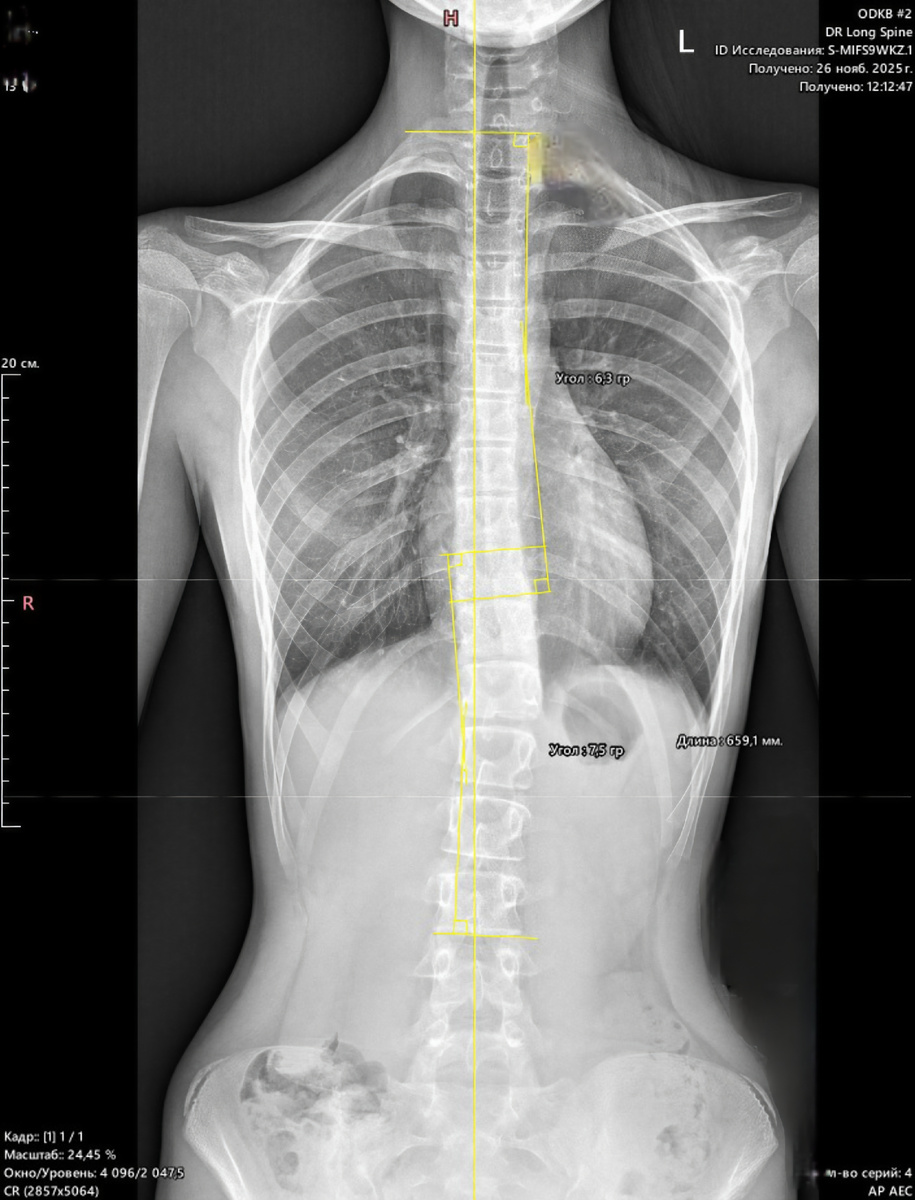

На послСднСм ΠΊΠΎΠ½Ρ‚Ρ€ΠΎΠ»ΡŒΠ½ΠΎΠΌ Ρ€Π΅Π½Ρ‚Π³Π΅Π½Π΅ (сдСлан Π‘Π•Π— корсСта), ΠΌΡ‹ зафиксировали:

β€’ Грудная Π΄ΡƒΠ³Π°: 6Β° (I ΡΡ‚Π΅ΠΏΠ΅Π½ΡŒ)

β€’ ΠŸΠΎΡΡΠ½ΠΈΡ‡Π½Π°Ρ Π΄ΡƒΠ³Π°: 7Β° (I ΡΡ‚Π΅ΠΏΠ΅Π½ΡŒ)

Π­Ρ‚ΠΎ Π’Π•Π›Π˜ΠšΠžΠ›Π•ΠŸΠΠ«Π™ Ρ€Π΅Π·ΡƒΠ»ΡŒΡ‚Π°Ρ‚!

ΠœΡ‹ добились РЕГРЕББА III стСпСни сколиоза Π΄ΠΎ минимальной I стСпСни Π·Π° счСт ΡƒΠΏΠΎΡ€Π½ΠΎΠΉ консСрвативной Ρ€Π°Π±ΠΎΡ‚Ρ‹!

Π­Ρ‚ΠΎ ΠΏΠΎΠ΄Ρ‚Π²Π΅Ρ€ΠΆΠ΄Π°Π΅Ρ‚, Ρ‡Ρ‚ΠΎ Π΄Π°ΠΆΠ΅ ΠΏΡ€ΠΈ ΡƒΠ³Ρ€ΠΎΠΆΠ°ΡŽΡ‰ΠΈΡ… ΡƒΠ³Π»Π°Ρ…, дисциплина Π΄Π°Π΅Ρ‚ шанс Π½Π° исправлСниС!